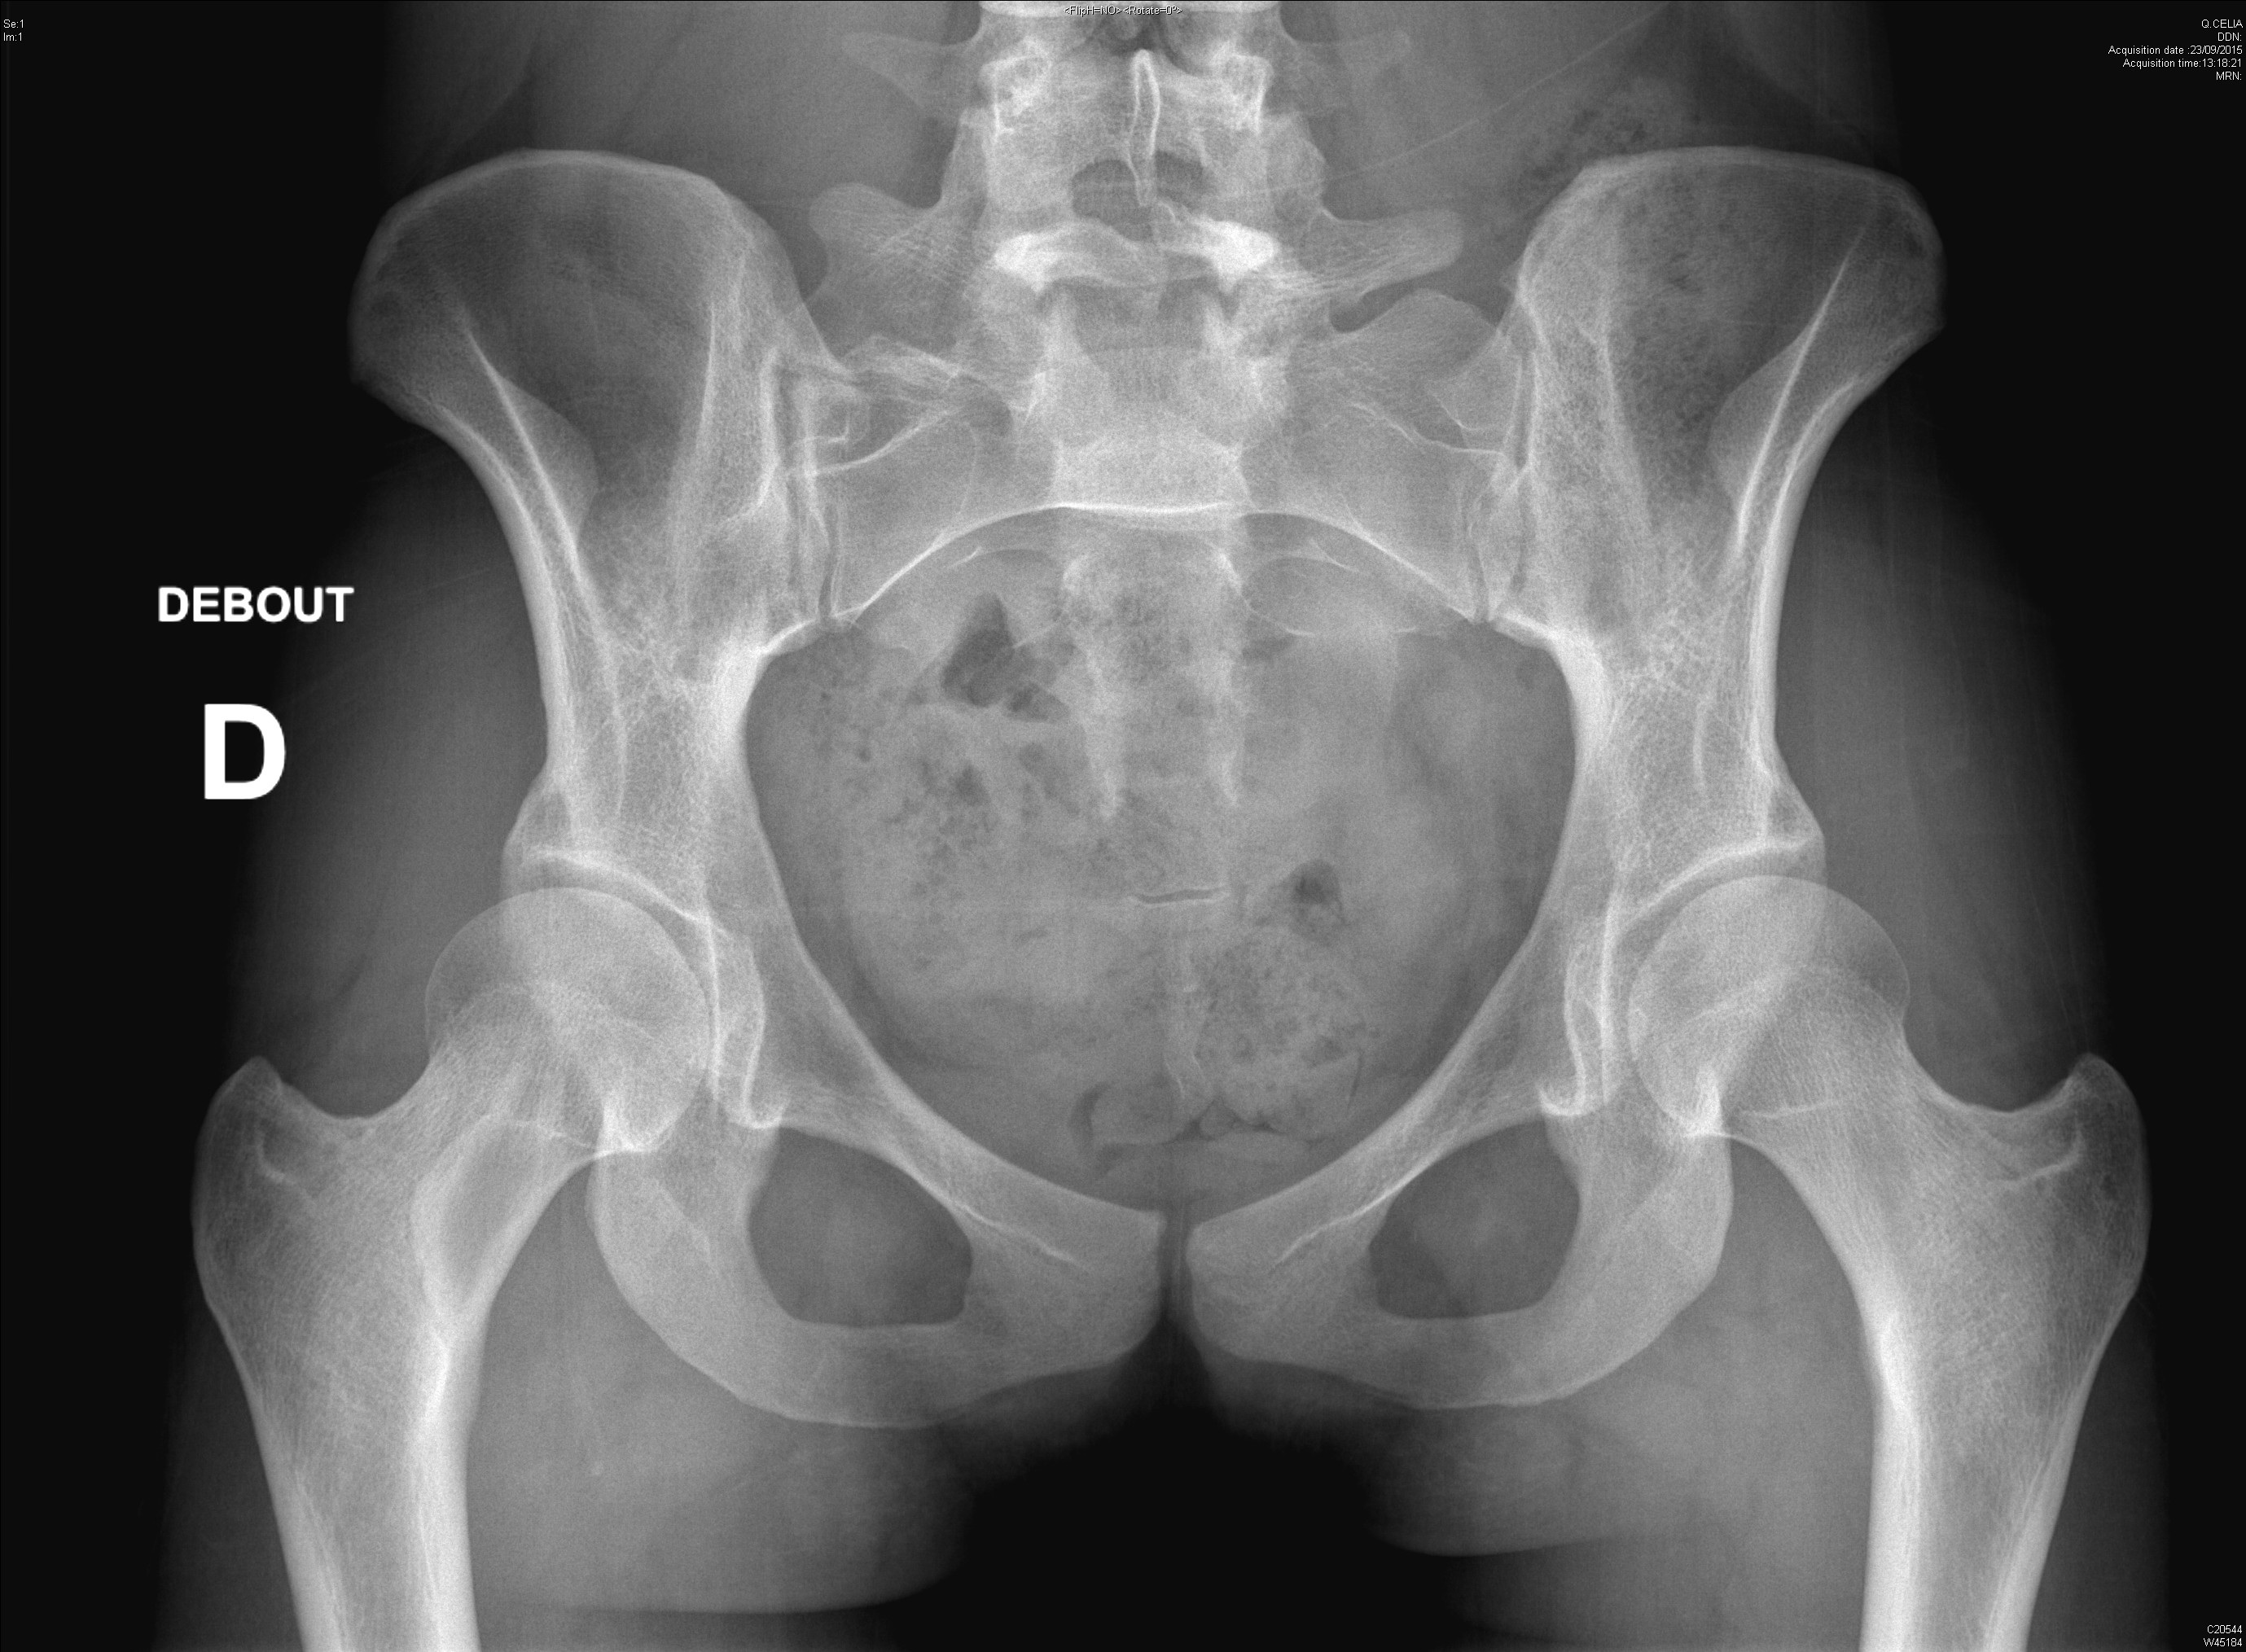

Radiographie retrouvant une dysplasie acétabulaire bilatérale ainsi qu'une lésion de dysplasie fibreuse du col fémoral droit chez une jeune fille